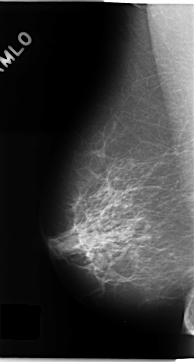

C_0133_1.RIGHT_MLO

RIGHT_MLO LINES 4704 PIXELS_PER_LINE 2520 BITS_PER_PIXEL 12 RESOLUTION 50 NON_OVERLAY